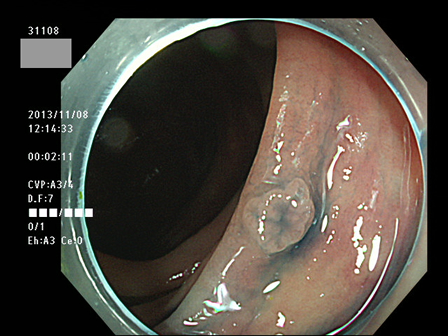

上記100名より抽出した平坦・陥凹型腺腫(=癌化の危険が高いが見落としやすい病変)の内視鏡写真